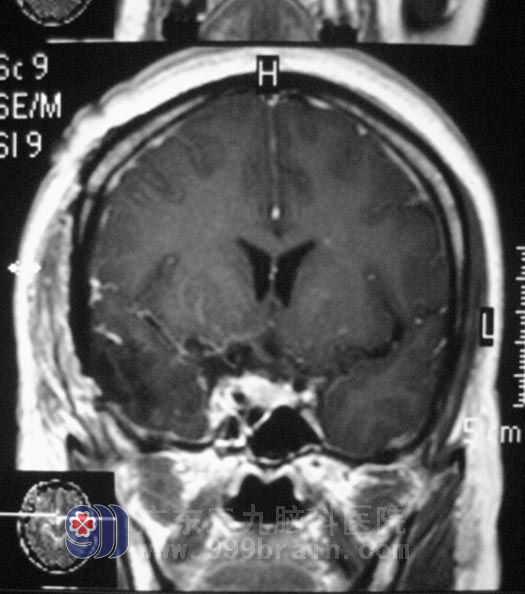

神经外五科鲁明主任分析后指出:许女士右眼视力下降与右侧鞍区占位有关,从头颅MRI上看,右侧鞍区占位内有许多血管通过,右侧颈内动脉被肿瘤包裹,有受压变细,术中分离肿瘤可能损伤颈内动脉。经过慎重考虑决定先行造影栓塞后再行手术治疗,避免术中大量出血,减少手术的风险性。3月20日,许女士在介入室行肿瘤部分供血血管栓塞术。3月22日,由鲁明主任主刀,在全麻下行“右侧蝶骨嵴脑膜瘤切除术”, 术中见肿瘤位于右侧中颅窝底,其基底部位于右侧蝶骨嵴、前床突位置,包绕右侧颈内动脉并延伸至对侧鞍旁,右侧视神经被肿瘤包绕并向上抬起,右侧动眼神经、外展神经被肿瘤压迫位于肿瘤外侧,肿瘤质地较软,血供丰富。显微镜下小心分离,将肿瘤分块全切,椎动脉及其分支位于肿瘤后下方,过程中右侧颈内动脉及其分支、椎动脉及其分支、双侧视神经、外展神经及动眼神经保护完好,手术成功完成。术后患者病理结果为:(右侧蝶骨嵴)脑膜皮细胞型脑膜瘤,WHOI级。

▲手术后影像